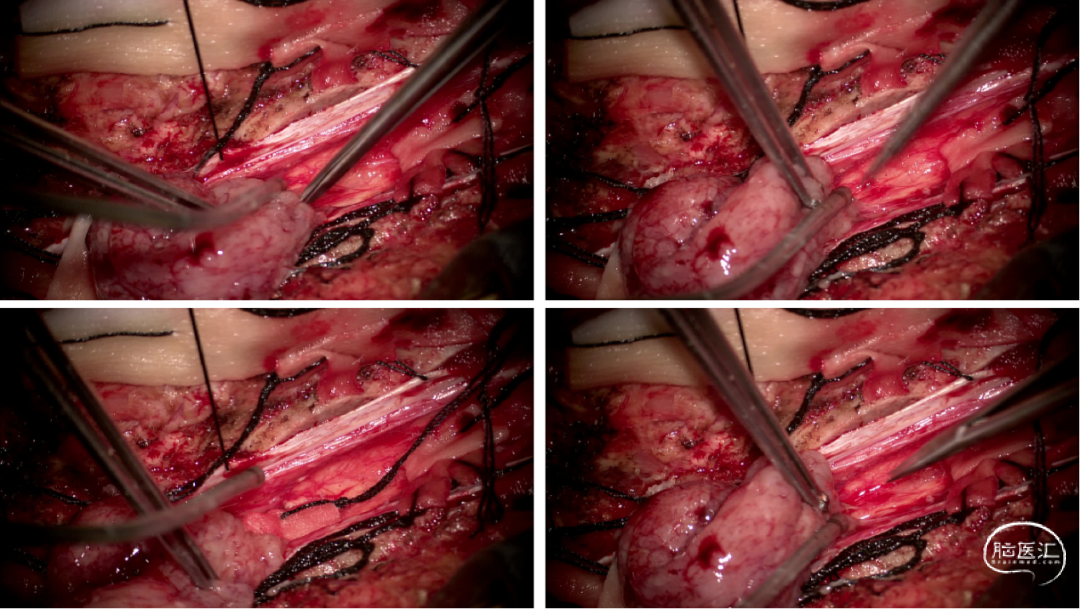

手术情况

硬脊膜张力高,脊髓向背侧膨出,与脊髓腹侧粘连紧密,肿瘤挤压脊髓,肿瘤边界分离,减少对胸髓的牵拉,降低了术后患者神经功能发生的概率,术后患者肢体麻木症状改善。